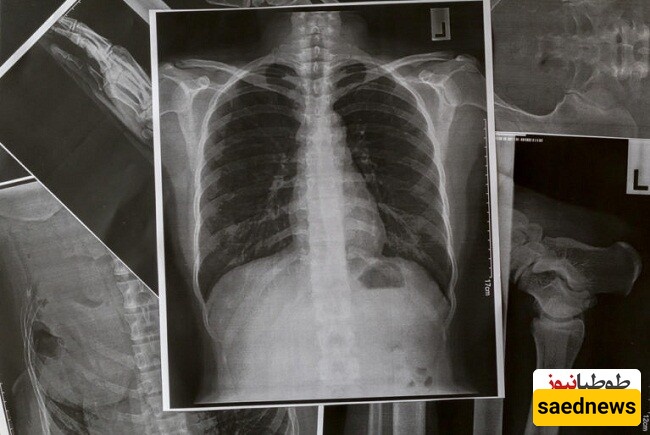

8. Pneumonia

Continuous cough with brown or green mucus, fever, and shortness of breath can indicate pneumonia. Individuals with chronic lung conditions are at higher risk, but healthy people can also be affected. Immediate medical attention is required as pneumonia can be life-threatening.